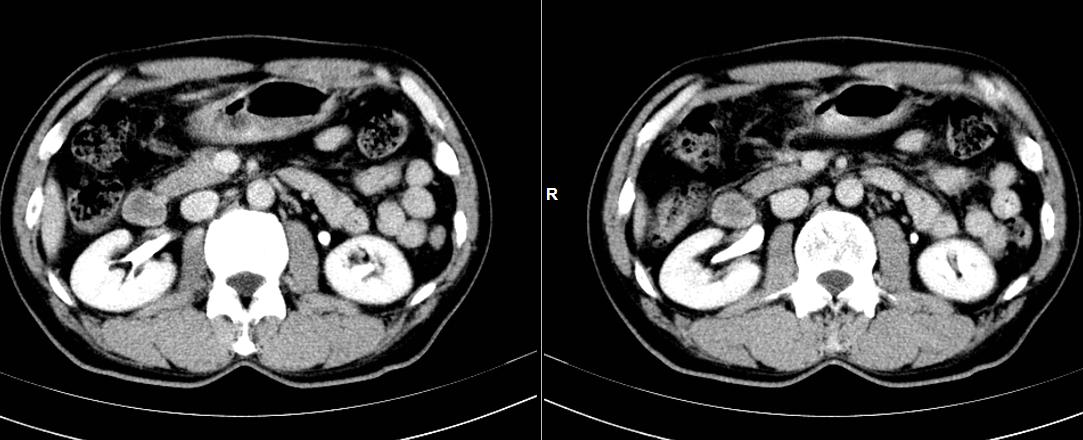

本帖最后由 cefcmj 于 2015-7-26 12:35 编辑 男性,51岁,右上腹痛,B超提示肝内占位。

肝左叶可见多个结节,部分外突,增强呈快进快出,考虑肝癌可能性大。

综合考虑肝癌并肝内转移。增强方式不是很典型。再仔细看看门脉左支。临床情况怎么样,AFP高吗?

肝左叶外生性肝癌。